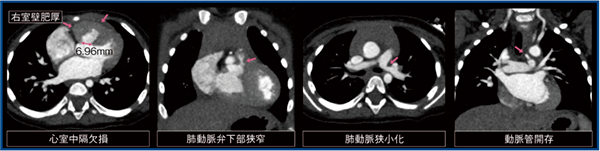

図2は,ファロー四徴症疑いの小児における心電図同期CT画像である。本症例は110bpmと高心拍であるが,0.24s/rotのハーフ再構成を用いることで,心室中隔欠損,肺動脈弁下部狭窄,左肺動脈屈曲部の狭小化,動脈管開存を画像のブレなく明瞭に描出可能であった。

図2 ファロー四徴症疑い症例の心電図同期CT画像(1歳,女児)